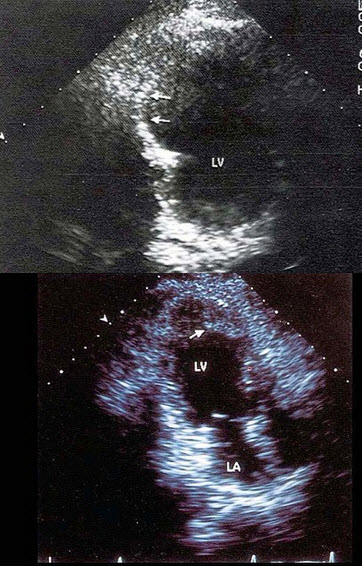

42、单项选择题

该图表明()

A.房室连接一致

B.房室连接不一致

C.大动脉转位

D.房室不定位

E.以上都不是